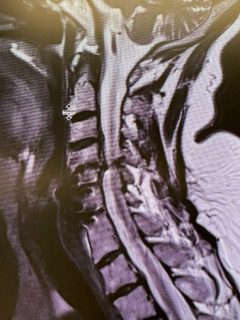

This 57 year-old male presents with severe neck, left shoulder and arm pain and weakness in his hand since being involved in a motor vehicle accident […]

Patient is a 60-year-old female who presents with severe right upper extremity pain and weakness over several months. She had a prior C6-7 ACDF with […]